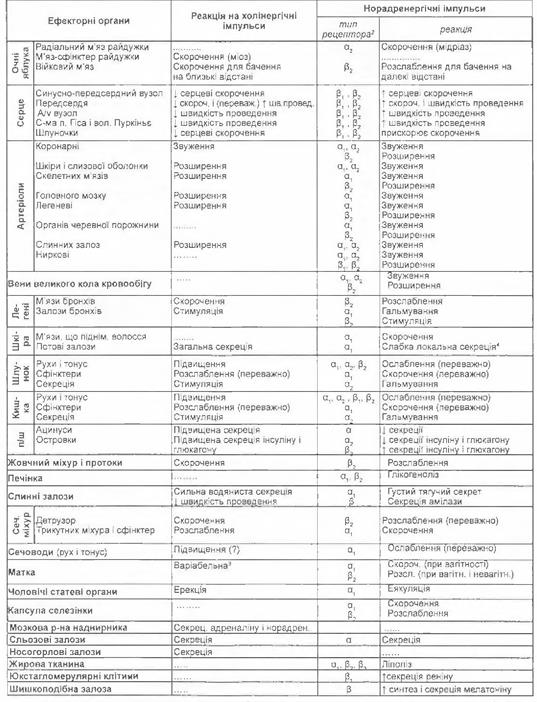

Реакція ефекторних органів на імпульси ВНС і циркулюючих катехоламінів

|

|

|

|